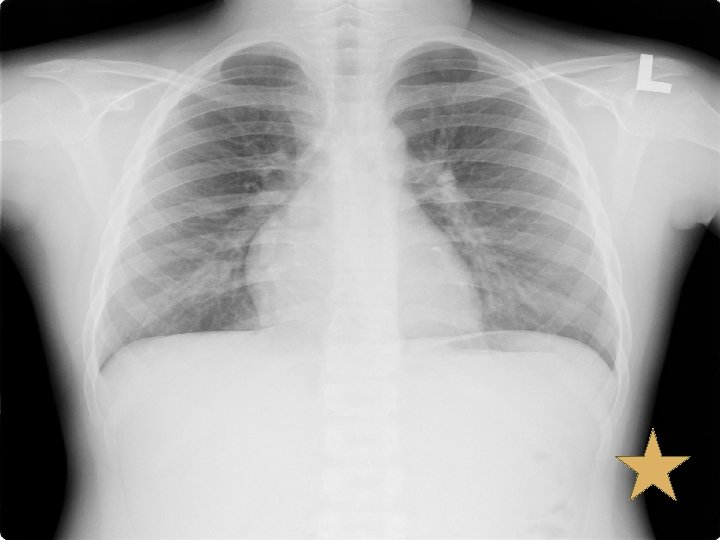

PET/CT Report v. Multiple hypermetabolic bilateral cervical lymph nodes (more on the left), likely nodal metastases. v. Multiple pulmonary nodules, probably pulmonary metastases. v. Multiple small hypermetabolic poorly osteolytic and nonosteolytic lesion, probably inhomogeneous marrow activity in child or foci of marrow infiltration. Correlation with other imaging modality such as bone scan is recommended

Bone Scan v. Bone scan (17/08/52) v. Bone lesion at skull is corresponding with multiple geographic lytic lesions without sclerotic rim and some blastic lesions in diploic space of bilateral parietal bone, likely bone metastases. Bone lesion at C 2 vertebral body, pelvic rim, right acetabulum, head, proximal, mid shaft and distal right femur, likely due to bone metastases as correlated with lytic lesion seen on PET/CT.

X-Ray